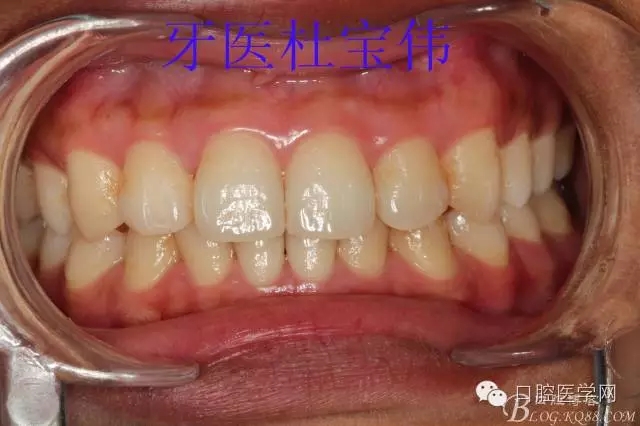

術(shù)后照片